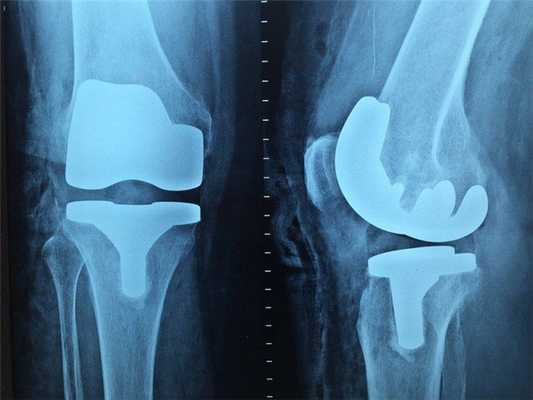

- Рентгенография. На этапе первичной диагностики больных с подозрением на фибросаркому направляют на рентгенологическое исследование. По данным рентгенографии определяется узел овоидной формы с однородной структурой и нечеткими границами. В области узла могут выявляться участки обызвествления, при распространенных процессах отмечается узурация кости.

- Томография. Для определения стадии заболевания и получения более полных данных о структуре, размере и расположении фибросаркомы при необходимости назначают КТ и МРТ.